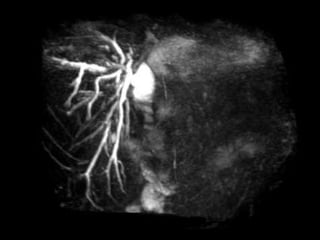

PATOGÊNESE  Isquemia Lesões complexas Strasberg E3-5, Bismuth>3 CT angio MRA Angiografia

PATOGÊNESE IsquemiaLesões complexas Strasberg E3-5, Bismuth>3 CT angio MRA Angiografia